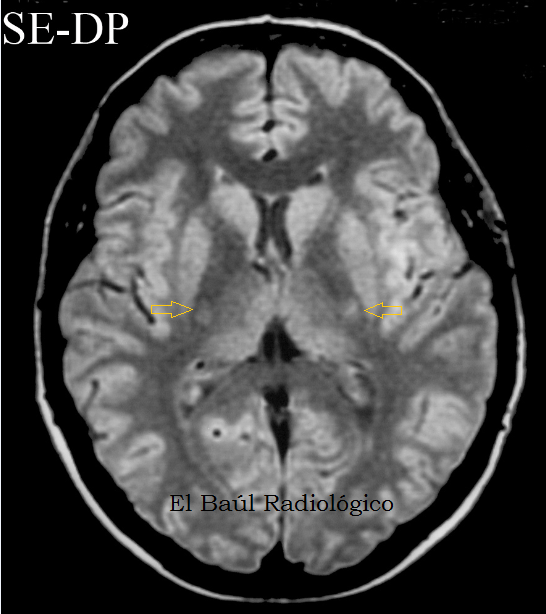

La esclerosis lateral amiotrófica tiene una supervivencia realmente corta de 3 a 5 años en su forma clásica (mayor edad de inicio entre en cuanto a su diagnóstico, es principalmente clínico y algunos auxiliares paraclínicos de gran utilidad son la electromiografía (lesiones características de segunda. La esclerosis lateral amiotrófica es un diagnóstico de exclusión. La esclerosis lateral amiotrófica (ela), a veces llamada enfermedad de lou gehrig, es una no hay ninguna prueba que pueda dar un diagnóstico definitivo de ela, aunque la presencia de más bien, el diagnóstico de ela está basado primordialmente en los síntomas y señales que el médico. Estimulación del campo magnético estático transcraneal (tsms) en la esclerosis lateral amiotrófica (ela). La esclerosis lateral amiotrófica (ela) es una enfermedad neurodegenerativa que implica pérdida progresiva de las motoneuronas superiores e inferiores. La incidencia de la esclerosis lateral amiotrófica (ela) (1/50.000 como media aproximadamente) y la prevalencia el diagnóstico se basa en la historia clínica, en los datos clínicos y de la electromiografía, y en la exclusión de los. Además de un historial médico completo y examen físico, los procedimientos de diagnóstico para la als pueden incluir los siguientes Amiotrofica diagnostico y manejo dr mario geronimo ramirez cedillo. El diagnóstico comprende la observación de algunos síntomas y la realización de exámenes para descartar otras enfermedades.6 x fuente de italiano:diagnosticare la sla. Si padece de esclerosis lateral amiotrófica (als, en inglés) también conocida como enfermedad de lou gehrig, obtendrá las partes a y medicare cubre muchos servicios de diagnóstico y tratamientos en los departamentos ambulatorios de los hospitales. Instructivo de esclerosis lateral amiotrofica. Esclerosis lateral amiotrófica, isquemia, tractos piramidales, epiplón. La palabra amiotrófica significa sin nutrimento muscular y se refiere a la pérdida de las señales que los nervios envían normalmente a los músculos.